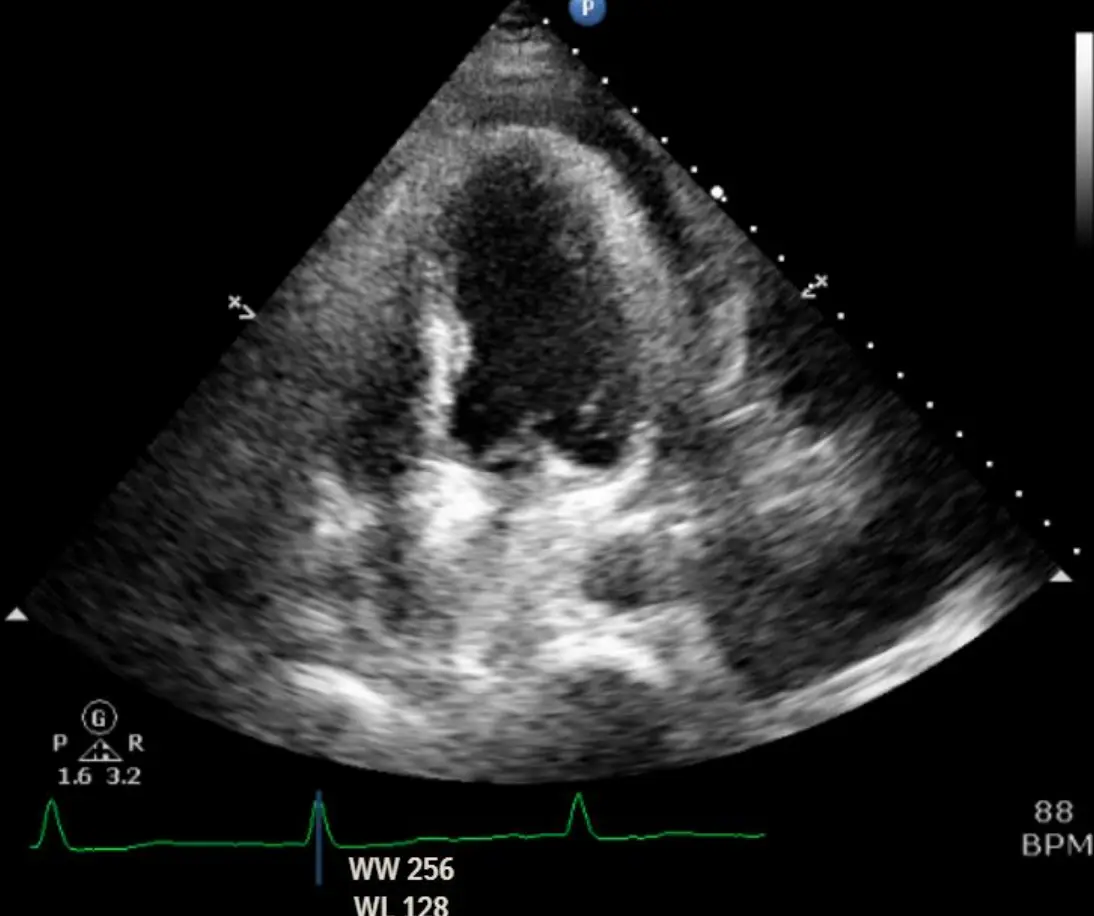

3. Echocardiogram:

• 四腔像可見心肌與心包之間廣泛無回聲帶;右房、右室於早期舒張期呈輕度塌陷。